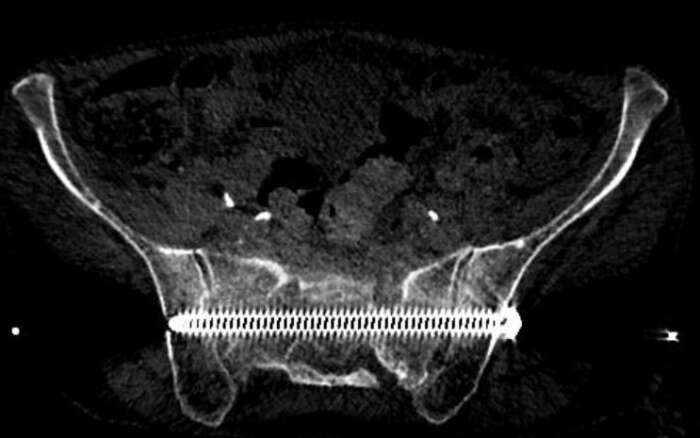

In diesem Beispiel war die Patientin vier Wochen nach einem Sturz nur noch mit Krücken und mit Schmerzen mobil. Die Computer Tomographie (CT) zeigte einen nicht verschobenen Bruch des Kreuzbeins und eine leicht verschobene Fraktur des Schambeins. Während der Operation implantierten wir CT-gesteuert zwei 7,3-mm-Schrauben. Die Schrauben gingen durch beide Ilio-Sakralgelenke und erste und zweite sakrale Wirbelkörper. Die Patientin konnte am nächsten Tag nach Hause entlassen werden und war schmerzfrei mobil.

Röntgen Becken nach Implantation zweier 7.3 mm Schrauben quer durch das Becken und Kreuzbein